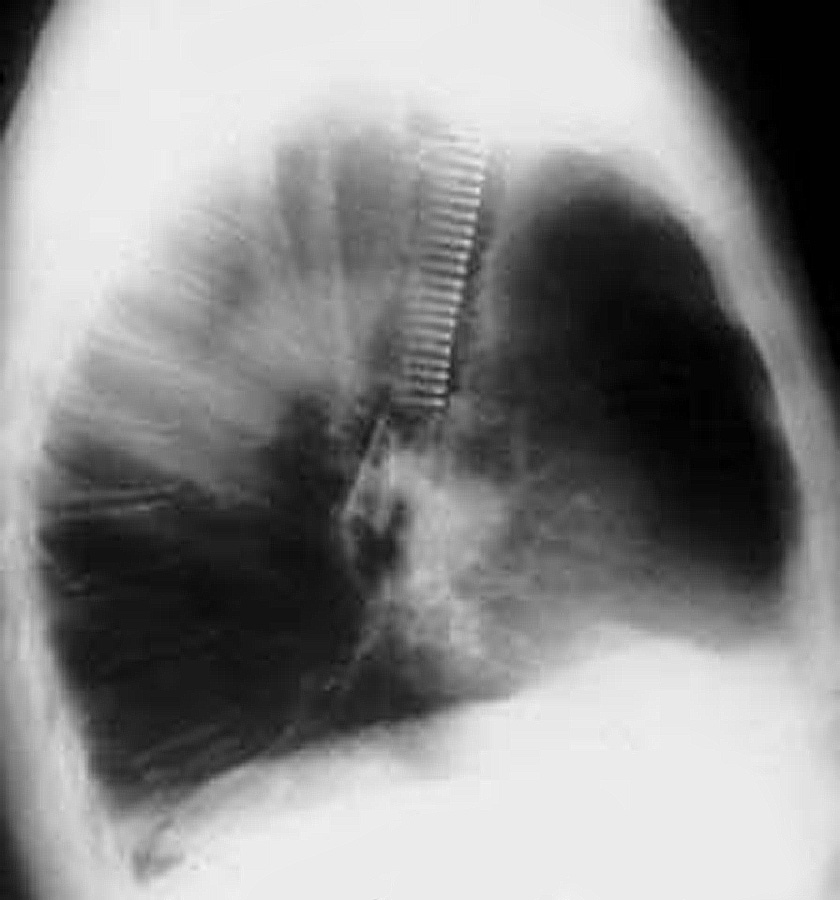

Freitag and colleagues extensively described the use of the Dynamic stent (Figures 15, 16) in patients with benign and malignant airway obstructions. This stent shows the potential advantage of having a flexible “membranous wall” able to squeeze down during coughing, facilitating mucous clearance. Placement of this stent is potentially more complicated but dedicated delivery grasping forceps have been designed to facilitate it (Figure 17). Results are promising for management of distal tracheal, carinal, and mainstem bronchial obstructions.

| Figure 15: Dynamic Freitag stent | Figure 16: Chest x ray: lateral view with the Dynamic stent in place | Figure 17: Dedicated Dynamic stent introducer |